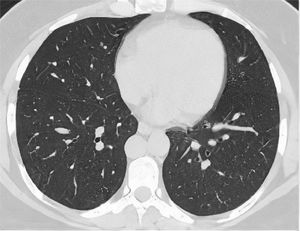

After classification, the data underwent interobserver agreement analysis, divergent interpretations were resolved by consensus. Figures 2 to 4 shows examples of our cases and the corresponding RAD-Covid Score.

RAD-Covid Score 0. Male patient, 42 years old, with 2 days of symptoms and Covid-19 infection confirmed by rt-PCR. The axial chest CT image shows no relevant pulmonary changes (normal chest CT). The chest CT can be negative in the first days of symptoms (the literature reports up to 50% normal CT in patients with less than 2 days of symptoms) (20).